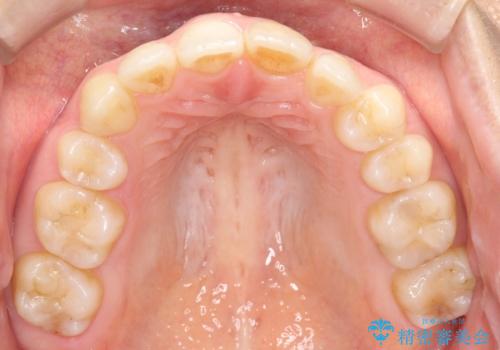

矯正後の後戻り インビザラインで改善

- 前歯のガタツキが気になると来院されました。

マウスピース矯正治療を選択しました。